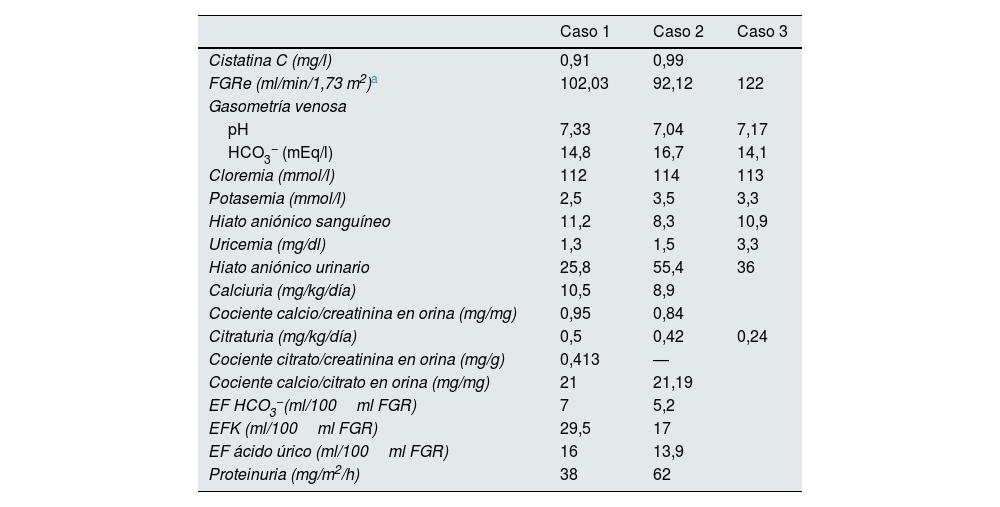

Exámenes bioquímicos sanguíneos y urinarios

| Caso 1 | Caso 2 | Caso 3 | |

|---|---|---|---|

| Cistatina C (mg/l) | 0,91 | 0,99 | |

| FGRe (ml/min/1,73 m2)a | 102,03 | 92,12 | 122 |

| Gasometría venosa | |||

| pH | 7,33 | 7,04 | 7,17 |

| HCO3− (mEq/l) | 14,8 | 16,7 | 14,1 |

| Cloremia (mmol/l) | 112 | 114 | 113 |

| Potasemia (mmol/l) | 2,5 | 3,5 | 3,3 |

| Hiato aniónico sanguíneo | 11,2 | 8,3 | 10,9 |

| Uricemia (mg/dl) | 1,3 | 1,5 | 3,3 |

| Hiato aniónico urinario | 25,8 | 55,4 | 36 |

| Calciuria (mg/kg/día) | 10,5 | 8,9 | |

| Cociente calcio/creatinina en orina (mg/mg) | 0,95 | 0,84 | |

| Citraturia (mg/kg/día) | 0,5 | 0,42 | 0,24 |

| Cociente citrato/creatinina en orina (mg/g) | 0,413 | — | |

| Cociente calcio/citrato en orina (mg/mg) | 21 | 21,19 | |

| EF HCO3−(ml/100ml FGR) | 7 | 5,2 | |

| EFK (ml/100ml FGR) | 29,5 | 17 | |

| EF ácido úrico (ml/100ml FGR) | 16 | 13,9 | |

| Proteinuria (mg/m2/h) | 38 | 62 | |

EF: excreción fraccional; EFK: excreción fraccional de potasio; FGR: filtrado glomerular renal; FGRe: filtrado glomerular renal estimado; HCO3−: anión bicarbonato.